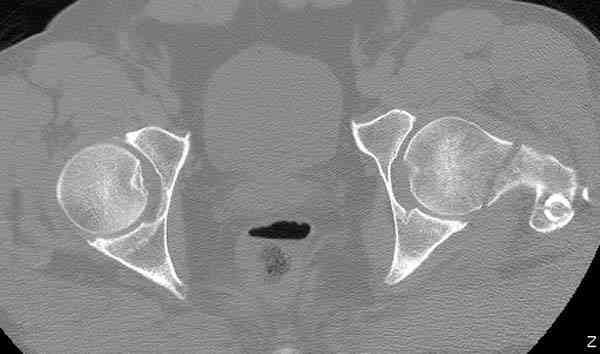

Здесь представлены снимки больного 65 лет, поступившего с диагнозом перелом

бедра после автоаварии.

В первый же день произведено антеградное штифтованием DePuy Trochanteric Nail.

На второй день (7) обнаружен пропущенный перелом,

сделаны Компьютерная Томограмма

и проведены шурурпы через и спереди штифта без удаления.

Послеоперационные снимки